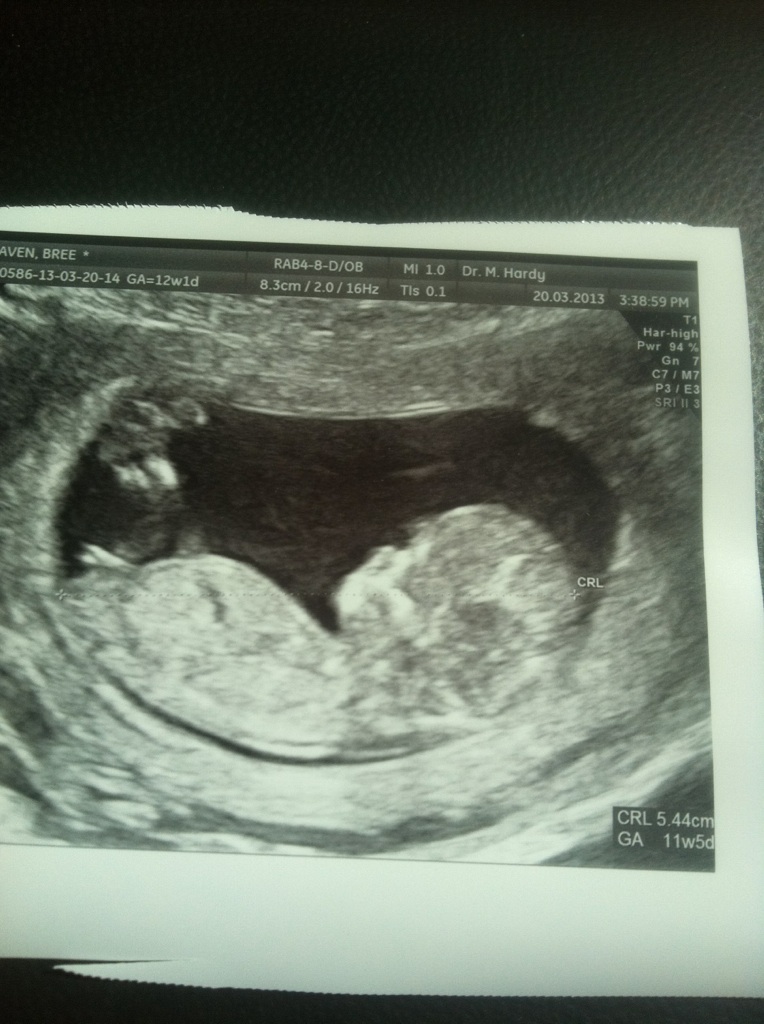

This is the U fork nub

Attachment 9960